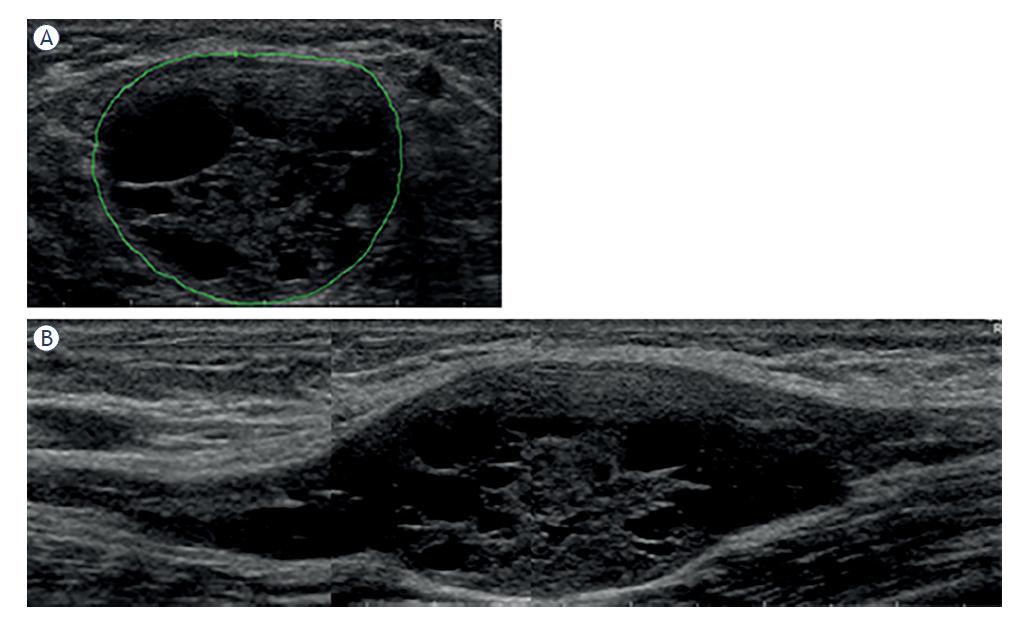

Morphological features of peripheral nerve tumors (PNTs) found on ultrasonographic (US) examination5 of individual patients

| # | Ratio | Shape | Contour | Encapsulation | Echo texture | Nerve position | Nerve transition | Number | Tumor diagnosis |

|---|---|---|---|---|---|---|---|---|---|

| 1 | 5 | Fusiform | Lobulated | Partial | Heterogeneous | Central | Infiltrative | Single | Neurofibroma |

| 2 | ? | Lobulated | Partial | Heterogeneous | ? | ? | Several | Schwannoma* | |

| 3 | 6 | Fusiform | Smooth | Whole | Heterogeneous | Central | Poorly defined | Single | Schwannoma |

| 4 | 6 | Fusiform | Fusiform | None | Heterogeneous | Central | Infiltrative | Several | Neurofibroma |

| 5 | 8 | Fusiform | Lobulated | Partial | Heterogeneous | Central | Infiltrative | Single | Perineurioma |

| 6 | > 10 | Fusiform | Lobulated | Partial | Heterogeneous | ? | ? | Single | Perineurioma |

| 7 | 6 | Fusiform | Smooth | None | Homogenous | Central | Infiltrative | Single | Perineurioma |

| 8 | 3 | Oval | Smooth | Whole | Heterogeneous | Central | Poorly defined | Single | Schwannoma* |

| 9 | > 10 | Fusiform | Lobulated | Partial | Heterogeneous | Eccentric | Infiltrative | Single | Neurofibroma |

| 10 | 5 | Fusiform | Smooth | Whole | Heterogeneous | Central | Infiltrative | Several | Perineurioma |

| 11 | 1,5 | Oval | Smooth | Whole | Homogenous | Eccentric | ? | Single | Schwannoma* |

| 12 | 2,5 | Oval | Smooth | Whole | Heterogeneous | Central | Poorly defined | Single | Schwannoma* |

| 13 | 2,5 | Oval | Smooth | Whole | Heterogeneous | Central | Poorly defined | Several | Neurofibroma |

| 14 | 4 | Fusiform | Lobulated | Partial | Heterogeneous | Central | Infiltrative | Several | Neurofibroma* |

| 15 | 1,7 | Oval | Smooth | Whole | Heterogeneous | Eccentric | Poorly defined | Single | Schwannoma |

Demographic, anatomical, clinical, electrodiagnostic (EDx) and ultrasonographic (US) features of patients with peripheral nerve tumors (PNTs)

| # | Gender | Age | Side | Nerve | Location | Symptoms & Signs | CMAP amp. (mV) | SNAP amp. (μ V) | Tumor CSA (mm2) | Tumor diagnosis | Other |

|---|---|---|---|---|---|---|---|---|---|---|---|

| 1 | Male | 69 | R | Ulnar | Elbow | AWS | 43 | Neurofibroma | |||

| 2 | Male | 24 | L | #Radial | Upper arm | W | 0.2 | 4 | 24 | Schwannoma* | NF2 |

| 3 | Male | 66 | R | Median | Forearm | Æ | 6.9 | 5 | 49 | Schwannoma | |

| 4 | Male | 16 | L | #Median | Upper arm | WS | 61 | Neurofibroma | NF1 | ||

| 5 | Female | 26 | R | Ulnar | Forearm | AWS | 0.2 | 0 | 30 | Perineurioma | |

| 6 | Female | 18 | L | Sciatic | Thigh | AWS | 0.4 | 0 | 109 | Perineurioma | |

| 7 | Female | 18 | R | Fibular | Knee | AWS | 0 | 0 | 47 | Perineurioma | |

| 8 | Male | 47 | L | Ulnar | Elbow | M | 7.6 | 3 | 348 | Schwannoma* | |

| 9 | Female | 58 | R | Median | Forearm | P | 7.6 | 16 | 45 | Neurofibroma | |

| 10 | Female | 22 | R | Sciatic | Thigh | AWS | 0 | 0 | 97 | Perineurioma | |

| 11 | Female | 34 | R | Tibial | Ankle | PAWS | 10.6 | 7 | 1250 | Schwannoma* | |

| 12 | Male | 63 | L | Ulnar | Elbow | L | 8.2 | 5 | 368 | Schwannoma* | |

| 13 | Female | 52 | R | #Ulnar | Forearm | 6.2 | 12 | 212 | Neurofibroma | NF? | |

| 14 | Male | 24 | R | #Median | Upper arm | P | 6.3 | 33 | 26 | Neurofibroma* | NF1 |

| 15 | Female | 33 | L | Tibial | Ankle | L | 92 | Schwannoma |